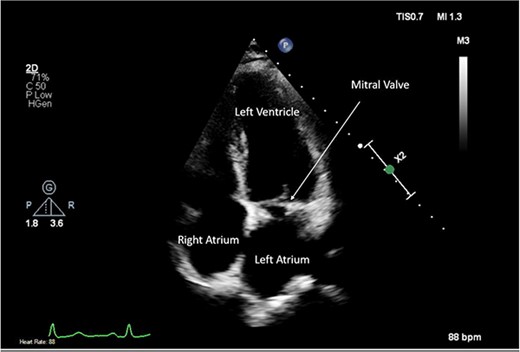

A CTPA was undertaken on Day 2, which excluded pulmonary embolism but confirmed bilateral peri-hilar consolidation and pleural effusions consistent with pneumonia. However, her pulmonary artery was dilated at 32 mm indicative of potential heart failure. On Day 5 of her ICU stay, a transthoracic echocardiogram was undertaken that revealed there to be severe mitral regurgitation including a mobile echogenic mass attached to the underside of the anterior mitral valve leaflet consistent with a vegetation (Figs 1 and 2).

Pre-operative TTE depicting mitral valve with vegetation (labelled).